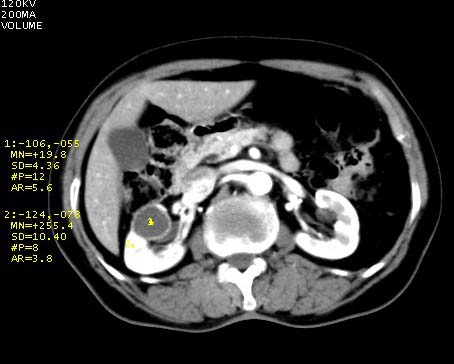

我又让查b超:钙乳性肾囊肿。

增强壁强化,考虑为囊肿。内部密度较高可能与含有较多的蛋白或钙质有关。“我又让查b超:钙乳性肾囊肿。”钙乳性肾囊肿是含有钙质?